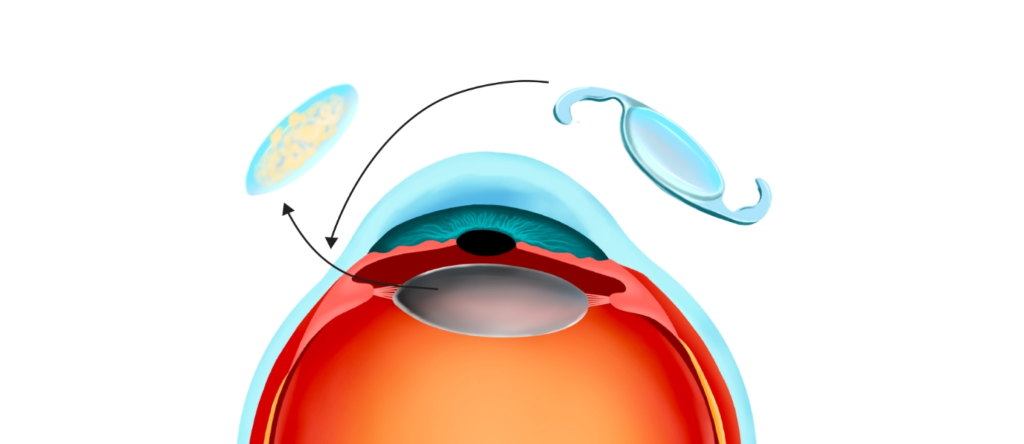

백내장 수술은 혼탁해진 눈의 렌즈(수정체)를 제거하고, 그 자리에 인공 렌즈(IOL)를 삽입하는 수술입니다.

백내장 수술 방법

인공수정체 삽입